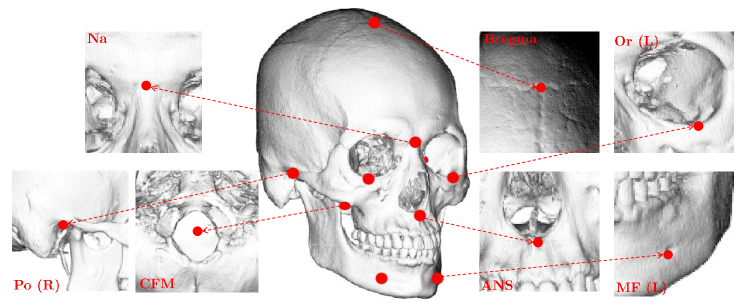

For ease of explanation, we begin by introducing the following notations. Five easy-to-find reference landmarks (CFM, Bregma, Na, and Po (L/R)) are used as the basis for constructing a coordinate system to determine the midsagittal and axial planes, and they were utilized for data normalization (methods for obtaining these five reference landmarks will be described in Section 2.1).

denotes a concatenated vector of landmarks (Bregma, CFM, Na, ANS, Or (L/R), and Po (L/R)) in the cranium and denotes a concatenated vector of landmarks (MF (L/R)) in the mandible. A reference landmark vector is defined by .

The first step of the proposed method is to find 10 reference landmarks from a given . Initially, a CT image is converted into a binarized image by (1). From , 2D illuminated images are generated by manipulating various lighting and viewing directions (see Figure 2). By applying VGGNet [Simonyan2014] to these illuminated images, the reference landmarks are accurately and automatically identified. This detection method is based on that presented in the recent study [Lee2019].

Using these identified reference landmarks, data normalization is conducted for efficient feature learning of skull shape variations in further steps. By applying uniform scaling with respect to the cranial volume, the landmark vector is normalized, wherein the cranial volume is defined via a product of the distance between the -coordinate of Po (L) and Po (R) (cranial length), the distance between the -coordinate of Po (L) and Na (depth), and the distance between the -coordinate of CFM and Bregma (height). This data normalization minimizes the positional dependencies of landmarks on the translation, rotation, and overall size of the skull; therefore, shape information of the skull (regarding facial deformities) can be effectively learned in further VAE-based steps. From here on, we will denote all landmark vectors as normalized vectors (e.g., and are normalized vectors for total landmarks and reference landmarks).

The detection of the 10 reference landmarks () provided very accurate and robust results (see Table 1 and Figure 8). These results almost meet clinical requirements, while the intra-observer repeatability is with a precision less than 1 mm and the overall median inter-observer precision is approximately 2 mm in the 3D landmarking system [Pittayapat2016].